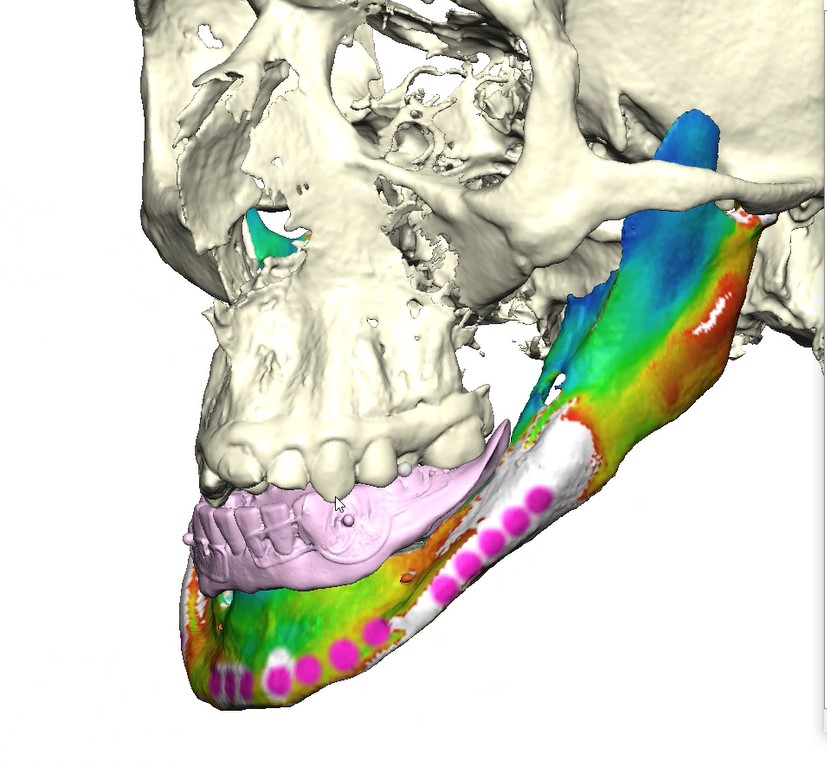

Records for this patient were collected using a dual-scan CBCT and intraoral scanning. A surgical planning session was completed with KLS Martin for the fabrication of a CAD-CAM subperiosteal implant system with immediate loading of a mandibular prototype (Figs 2-5).

A 3D-printed mandibular model with the subperiosteal system and prototype in place was also fabricated (Figs 6 and 7).

The custom titanium framework was trial seated and adapted accurately.

Due to the patient’s trismus, a transbuccal trocar system was used bilaterally to access posterior fixation sites, a technique commonly used in limited access mandibular fixation [17]. Locking screws were. placed under copious irrigation to achieve rigid stabilization (Fig 8).

• Stereophotography scans of the cast were performed with the prototype in place and after removal with ICam4D scan bodies using Trios 4 Wireless Pod (3Shape) (Figs 12-14).